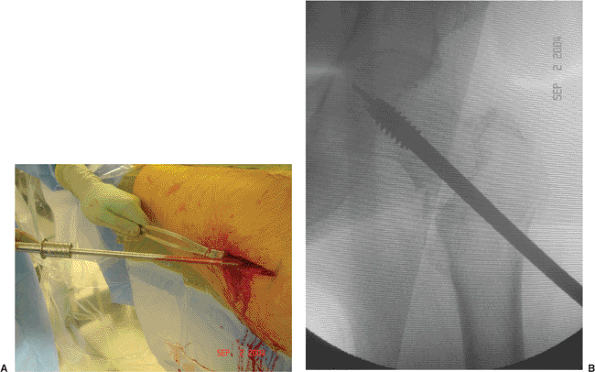

limb shortening, or medialization of the distal fragment. I prefer a

variable angle hip screw (VHS) (EBI, Parsippany, NJ) because it allows

some adjustment of the fracture alignment once the screw and plate

assembly has been implanted (Fig. 16.1). The

use of this implant also helps with inventory control as a single plate

can allow a range of plate angles, from 89 to 159 degrees. For unstable

Figure 16.1. A. Photograph of the VHS system demonstrating the adjustability of the plate angle. B. Radiographs after initial plate placement and (C) after use of the mechanism to bring the plate to the lateral femoral cortex.